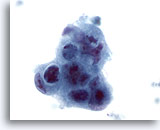

画像 1: 肝FNA – 良性肝細胞 良性肝細胞の小さな集塊。細胞は多角形のものもあれば円形のものもみられ、細胞境界は明瞭です。 核は中心性に位置し、周辺の細胞質は顆粒状を呈しています。細胞質内に色素沈着がみられます。小型の核小体がみられるものの、異型性および高N/C比は認められません。

60倍

画像 1

肝FNA – 良性肝細胞

良性肝細胞の小さな集塊。細胞は多角形のものもあれば円形のものもみられ、細胞境界は明瞭です。 核は中心性に位置し、周辺の細胞質は顆粒状を呈しています。細胞質内に色素沈着がみられます。小型の核小体がみられるものの、異型性および高N/C比は認められません。

60倍